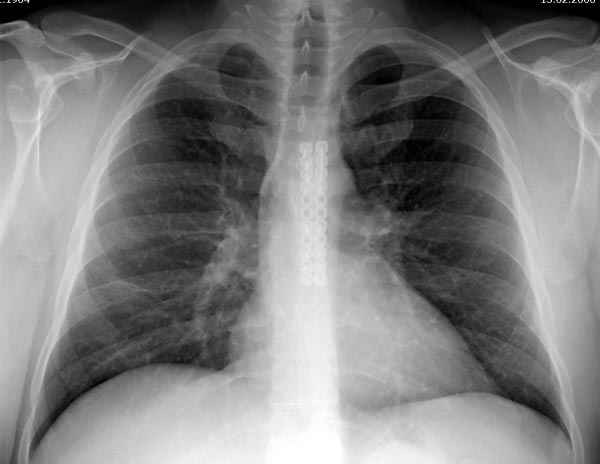

Может, имелись ввиду нарушения, связанные с изменением конфигурации средостения после эстетических операции на грудной клетки при врожденных: килевидных и воронкообразных деформациях, но в данном случае, кроме болевого синдрома, не думаю, что несросшиеся перелом грудины окажет серьёзное влияние на кардио-респираторные функции.

Пару лет назад коллега из грудной хирургии направил больного с хроническими жалобами на боли по поводу ложного сустава грудины.

Оперировали вместе с грудным хирургом и в нашем случае главной причиной была болезненность. Во время операции приняли все меры предосторожности недопущения прокола средостения (см. на 4 снимке близкий контур сердца!!)